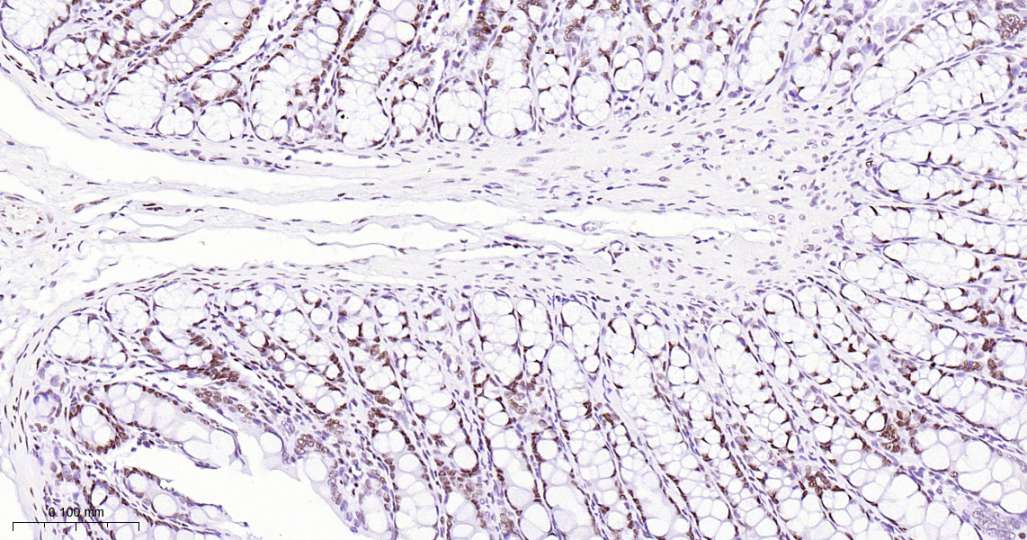

Immunohistochemical analysis of paraffin embedded Mouse colon tissue slide using IHC0626M (Mouse Phospho-POLR2A (Ser5) Kit).